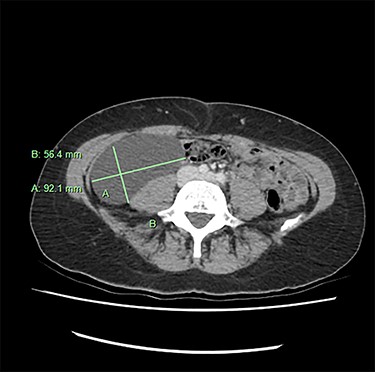

We present an extremely rare and isolated case of primary mixed serous and mucinous cystadenoma in a 49-year-old otherwise fit and healthy female patient. She was referred to our consultant with a history of discomfort on the right side of her abdomen for few years, which increased gradually with no other complains. The patient had further investigations conducted including computed tomography (CT) (Figs 1 and 2) that demonstrated the position and size of the lesion. The magnetic resonance imaging (MRI) revealed a large cystic lesion in the right retroperitoneal region shown in Figs 3 and 4. Her full blood count, inflammatory markers, urea and electrolytes and liver function tests were within the normal limit. Consequently, the patient had a laparoscopic resection of an isolated retroperitoneal cyst. At surgery, the cystic lesion seemed to be arising from mesentery and the lesion was dissected intact and completely excised. Histopathology revealed a benign mixed serous and mucinous cystadenoma as shown in Fig. 5. The patient was discharged from the hospital with no complications and fully recovered on follow-up review. Patient was discussed in a multidisciplinary team meeting and the recommendation was for no further management.

Serological investigations are not helping with providing a definitive diagnosis. Tumour markers such as, carbohydrate antigen (CA) 19–9, CA 15–3, CA 125, carcinoembryonic antigen (CEA), alpha feta protein have not been shown to be sensitive or specific. Some cases demonstrated an increase in CEA and CA 19–9 in associated with PRMC. However, these are isolated case studies. With regard to radiological investigation, the ultrasonography lacks specificity [11]. Radiological imaging, such as MRI and CT, plays an important role in describing and assessing the disease’s characteristics and the involvement of adjacent or distant structures of the mass. None of the modalities can exclude the malignant potential of the retroperitoneal masses [9], as the diagnostic value of CT and MRI is similar [12]. Predominantly male patients and the patients who present with solid nodules in the cyst on their radiology images have strong association with malignancy [13].